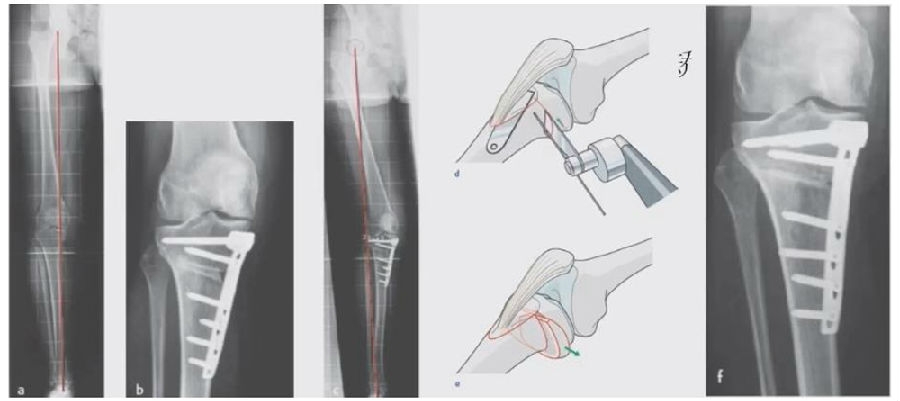

2、处理

(1)如果在手术台上,或是刚做完手术就发现矫正不良问题,此时比较简单。需要先跟患者进行沟通,在手术中直接将远端4颗螺钉卸下来,调整好力线后重新打入即可。但是注意要把远端单皮质螺钉换成双皮质螺钉。

(2)如果患者已经达到初始愈合,此时如果出现过度外翻,需要在内侧重新做内侧闭合楔。

(3)如果做完手术时间较长,出现过度矫正或矫正不足时,需要重新做力线分析,看一看力线在哪个方向可以再进行调整。胫骨侧有调整余地,就在胫骨侧进行调整;股骨侧需要调整,就在股骨侧进行调整。